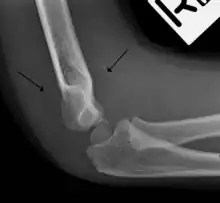

The fat pad sign, also known as the sail sign, is a potential finding on elbow radiography which suggests a fracture of one or more bones at the elbow. It may indicate an occult fracture that is not directly visible. Its name derives from the fact that it has the shape of a spinnaker (sail).[1] It is caused by displacement of the fat pad around the elbow joint. Both anterior and posterior fat pad signs exist, and both can be found on the same X-ray.

In addition to fracture, any process resulting in an elbow joint effusion may also demonstrate an abnormal fat pad sign. Increased intracapsular fluid is also seen in several conditions other than fracture and this produces the abnormal fat pad sign. (toxic synovitis, septic arthritis, Juvenile Rheumatoid Arthritis, osteomyelitis of the distal humeral physis and secondary septic joint). In these instances, history and clinical examination in addition laboratory results (WBC, ESR, CRP) will guide the provider in determining whether to treat the condition as an occult fracture or continue workup for other pathology.

The fat pad sign is invaluable in assessing for the presence of an intra-articular fracture of the elbow. An anterior fat pad is often normal. However a posterior fat pad seen on a lateral x-ray of the elbow is always abnormal. The patient will be unable to flex their elbow and requires orthopaedic input.[2]